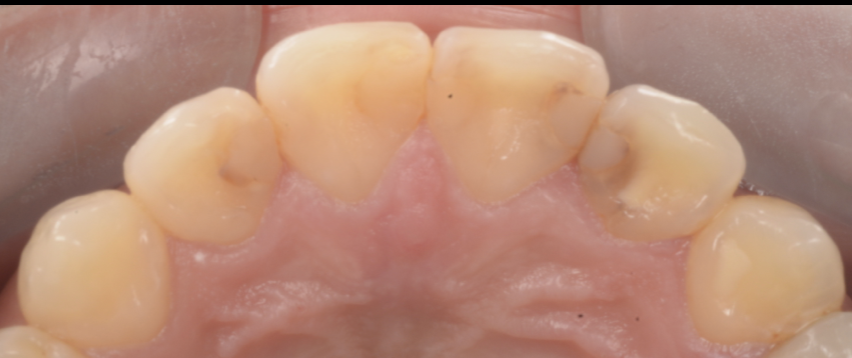

【今回の症例から】「詰めてあるのに、実は中で虫歯が進んでいた」

今回お伝えしたいのは、ここです。

患者さんは「詰め物が入っているから大丈夫」と思っていた。

見た目にも大きな痛みはない。

ただ、よく見ると着色が目立つ、そして詰め物が浮いているように見える。

そこで再治療のために詰め物を外してみると――

- 修復物の下で、虫歯が広がっていた

- 歯質が想像以上に脆く、削ると崩れる

- 結果として、当初の予想よりも歯の大半を失う形になってしまった

このケースは決して珍しくありません。

接着が破綻したところから微小漏洩が起き、そこに細菌が入り、見えない場所で増殖してしまう。

そして気づいた時には、表面の変色よりもずっと深部で病変が進行している――。